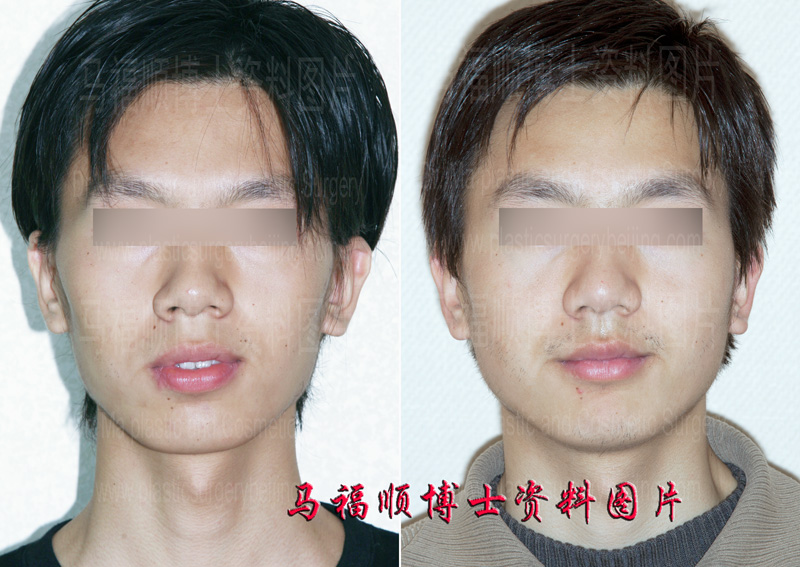

The handsome boy in this page had a bony face. On top of that he also had a protrusion mouth. His facial outline in profile is quite rough and irregular. He was also bothered with the parted lips in relax. He always tried to forcefully close his mouth hiding his teeth in attending important gatherings and in facing other people. However a prolonged forceful mouth closure would make himself uncomfortable on his lips. So he came and saw Dr. Ma for help. Upon the first contact Dr. Me believed his protrusion was not very serious and tried to convince him to forget the idea of surgery. But he insisted to do the surgery and told Dr. Ma that others hardly understand his psychological suffering from the condition. At the end Dr. Ma was convinced and a protrusion mouth plastic surgery was performed to setback the front part of his upper and lower jaws according to his degree of protrusion. When he came back for a follow-up later on he was satisfied with the after surgery result and told Dr. Ma that he never bothered to deliberately worry if his teeth were shown any more since then.

After the upper and lower jaws were pushed back the teeth are not show any more in relax.

The most obvious change in different groups of the before and after surgery comparison photos in this page is that the face of this handsome boy is not bony any more. Though this change could be caused by weight gain (as a matter of fact he didn’t gain weight after surgery), the dominate fact contributed to this change is the correction of the mouth protrusion. Because of the different aesthetic taste on face contour some people like bony face, while the others want a rounded one. This boy didn’t like bony face. So he insisted to get rid of the protrusion and felt happy with his post surgery result.

Another important change in this boys face is that his lips can meet each other in relax. In Dr. Ma’s opinion the parted lips and exposed teeth are the most bothering problems for protrusion mouth candidates. For people without mouth protrusion the teeth may show when smile. However for people with mouth protrusion the teeth may always show no matter happy or angry. Exposed teeth without the cooperation of facial express can be quite unnatural. This is the reason why so many mouth protrusion candidates insists on doing the surgery for a change. In another words the protrusion correction surgery dose not only change the look of the candidates but also relieve their psychological burden helping them gain confidence.